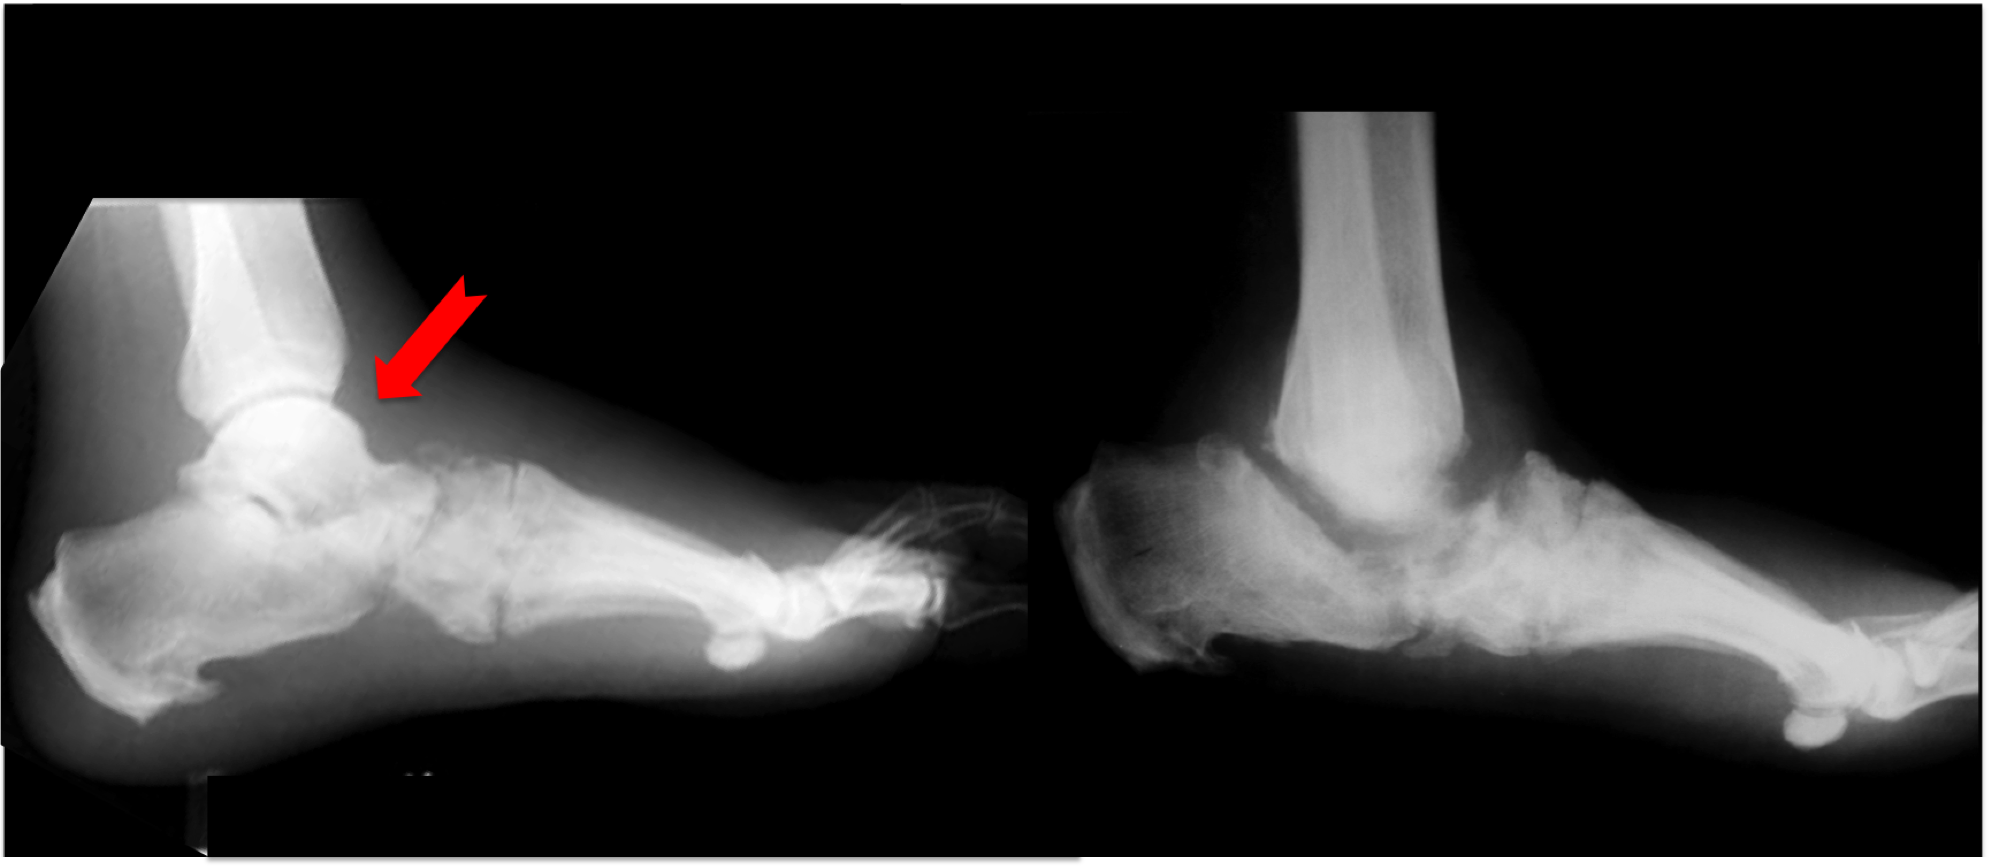

In the illustration below the red arrow points to the bone called the talus, on the left you can see it, in this case 6 months later the xray on the right shows that it has completely disappeared. This bone destruction is very common in the charcot process and creates a charcot ankle that is unstable and the patient may have difficulty walking since there is essentially no connection between the foot and rest of leg.